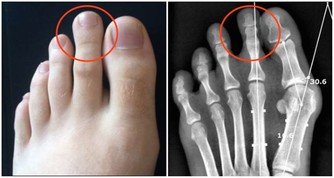

我的喉嚨偶爾會跑出米粒大小,黃白色的不明顆粒,

不會痛也不會不舒服,

但就是很臭,

這個症狀少說也有十幾年了,

我原本以為那是沒消化完的飯粒之類的,

後來我把關鍵字丟到谷歌,

才發現原來這是扁桃腺結石,

他耐心的用畫圖方式告訴我結石藏在扁桃腺的隱窩,不易清除,

所以通常會以開刀切除扁桃腺來解決,

扁桃體結石也會引起口臭

「扁 桃體結石引起的口臭並不少見,大人小孩都可能會出現」,北京中醫醫院耳鼻喉科副主任醫師姜志輝解釋。 扁桃體是人體的免疫器官,位於口咽側壁,包含有 很多隱窩,其中位於扁桃體上極的上隱窩就容易出現結石。 正常情況下扁桃腺隱窩沒有分泌物。 當扁桃體出現急慢性炎症時,就會有脫落上皮、大量淋巴細胞, 白細胞、以及各種致病菌自隱窩排出,若隱窩口堵塞而引起分泌物堆積,時間長了還會導致一些鎂、鈣等無機鹽沉積而引起結石。 這些腐敗的分泌物就會引起口 臭。

另 外,蔡立泰醫師也表示,扁桃腺結石通常看起來像白色或微黃色的小石頭,有時候吐出來時,可以把這些小石頭壓碎,並出現臭臭的味道。扁桃腺結石目前 大多認為是由食物的殘渣及壞菌卡在扁桃腺表面的隱窩中所形成。有些人會感覺到喉嚨卡卡的感覺,嚴重的患者更可能出現頭痛、咽喉疼痛、吞嚥困難、耳朵痛癢、 甚至嘔吐等情形。也因為這些細菌和食物的殘渣以及部分壞死組織的鈣化,所以可能在講話時散發出一些腐爛的臭味,也就是我們所謂的口臭。